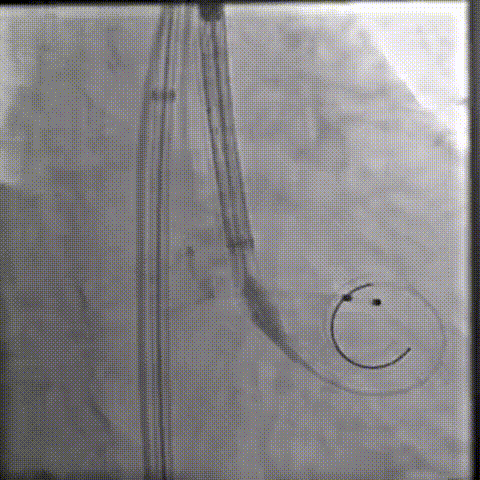

主动脉根部造影

20球囊预扩

初始定位